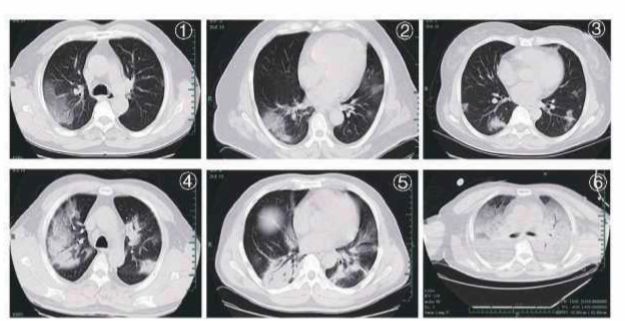

Examenele imagistice toracice sunt foarte valoroase în diagnosticul COVID-19, pentrueficacitatea monitorizării și pentru evaluarea pacienților înainte de externare. Este de preferat să se folosească aparatura de tip CT de rezoluție înaltă. Aparatele portabile pentru examenul Rx al toracelui sunt utile în cazul pacienților aflați în stare gravă și caresunt imobilizați. Examenul CT pentru evaluarea de bază a pacienților COVID-19 este de obicei realizat în ziua internării sau, dacă nu se atinge eficacitatea dorită a tratamentului, se poate realiza după 2 sau 3 zile. Dacă simptomele sunt stabile sau se ameliorează după tratament, se poate repeta CT-ul toracic după 5-7 zile. Se recomandă realizarea examenelor radiografice toracice zilnic, cu ajutorul aparatului portabil în cazul pacienților aflați în stare critică. În stadiile timpurii, leziunile provocate de COVID-19 se prezintă la examenul CT toracicsub formă de opacități multi-focale, de tip ground glass (in geam mat), localizate la periferia plămânilor, în zona subpleurală și în ambii lobi inferiori. Axul lung al leziunii este în mare parte paralel cu pleura. Se observă îngroșare la nivelul septului interlobular și îngroșare interstițială, intralobulară având aspect reticulat, subpleural, de tip “crazy paving” la nivelul anumitor opacități. La un număr mic de cazuri se pot observa leziuni singulare, locale sau nodulare distribuite în bronhii, cu modificări de tip ground glass la nivel periferic. Boala progresează de obicei în decursul a 7-10 zile, leziunile devenind mai mari și mai dense comparativ cu imaginile anterioare, iar leziunile au aspect de bronhogramă aerică. La cazurile critice se poate observa o consolidare generalizată, întregul pulmon are aspect opac fiind uneori denumit plămânul alb. După remiterea bolii, zonele opace de tip ground glass se pot resorbi complet însă anumite leziuni vor lăsa semne de fibroză sau desen reticular subpleural. Pacienții cu leziuni lobulare extinse trebuie ținuți sub observație pentru a observa o potențială exacerbare a bolii. Cei cu semne CT tipice COVID-19 ar trebui izolați și supușitestării continue prin detectarea acizilor nucleici chiar dacă acestea apar negative.